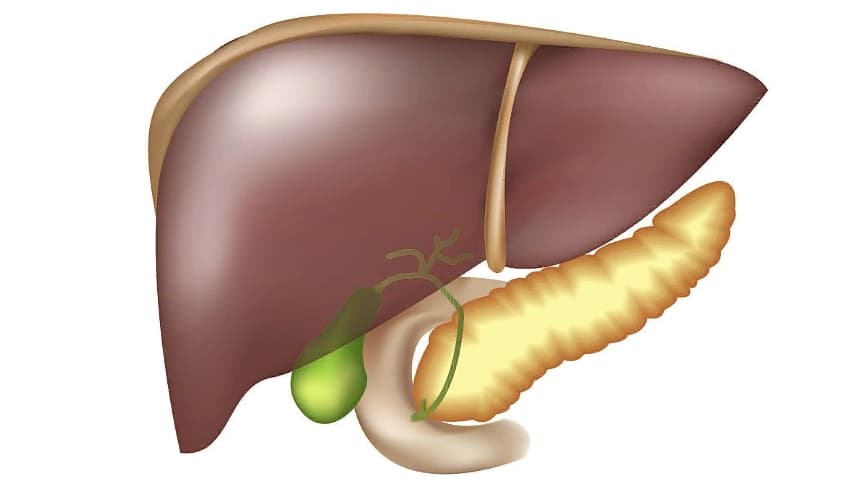

Анатомическое расположение поджелудочной железы

ПЖ располагается в брюшной полости, ближе к I–II позвонкам поясничного отдела позвоночника. Орган плотно крепится на задней стенке желудка, а 12-перстная кишка окружает ее, поддерживая в необходимом положении.

Параметры ПЖ взрослого человека в норме должны быть 20-25 см, вес – 70-80 граммов.

По анатомическому строению орган делится на 3 составных части: это головка, тело и хвост. Головкой ПЖ обращена к желчному протоку, тело находится за желудком, ближе к его нижней части. Рядом с телом в норме располагается поперечно-ободочная кишка. Хвостом ПЖ обращена к селезенке, и уходит к левому подреберью. По отношению к пупку, со стороны брюшной стенки, ПЖ расположена над ним, на 5-10 см выше.

Надо знать, где находится поджелудочная железа у человека, чтобы отличить боли от симптомов других патологий внутренних органов.